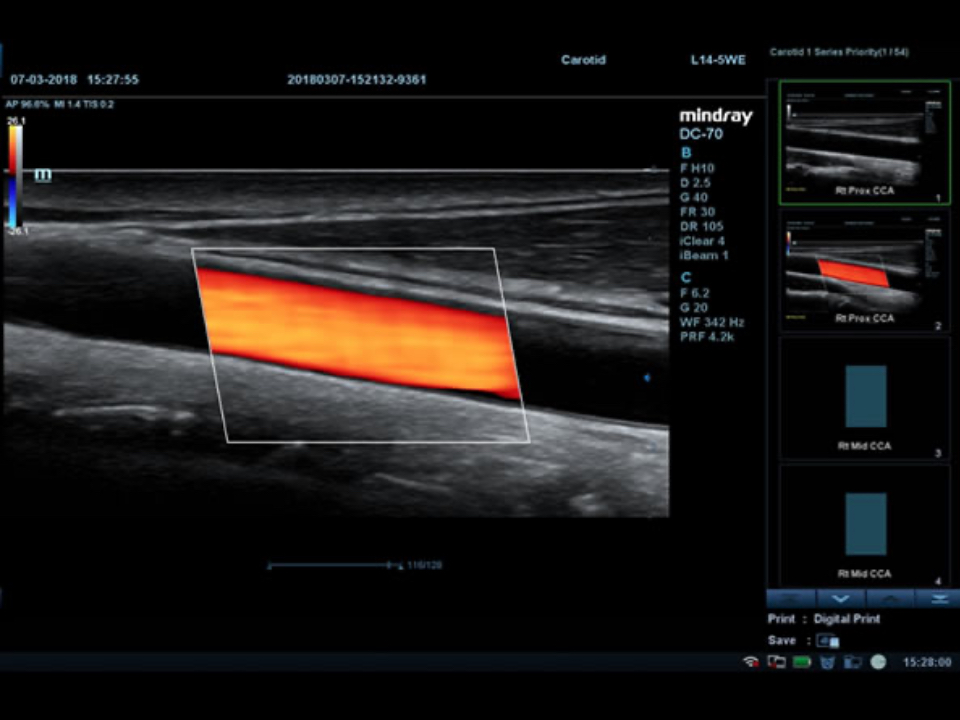

Smart Track

ItŌĆÖs Mindray unique feature to reduce repetitive, time-consuming scanning steps in vascular exams. Smart Track provides intelligent and real-time vessel tracking and real-time image optimization of Color and PW.